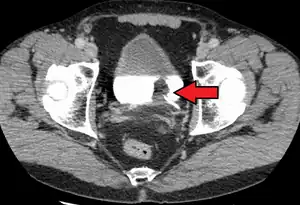

Bladder wall thickening due to cancer